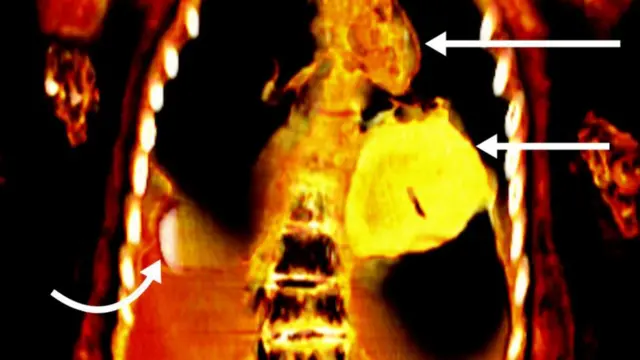

Знімки також показали, що під бинтами, якими було обгорнуто тіло покійного в процесі муміфікації, ховаються численні амулети 21 виду, до рота йому помістили золотий язик, а до грудної клітки - золотого жука-скарабея у формі серця.

Але особливе враження на докторку Салім справив амулет-скарабей. Вона навіть замовила його тривимірну копію, надруковану на принтері. За її словами, жрець записав на спинці у жука рядки з Книги мертвих, важливого давньоєгипетського тексту, який служив провідником для померлих у потойбічному світі, щоб допомогти юнакові в його останній подорожі.